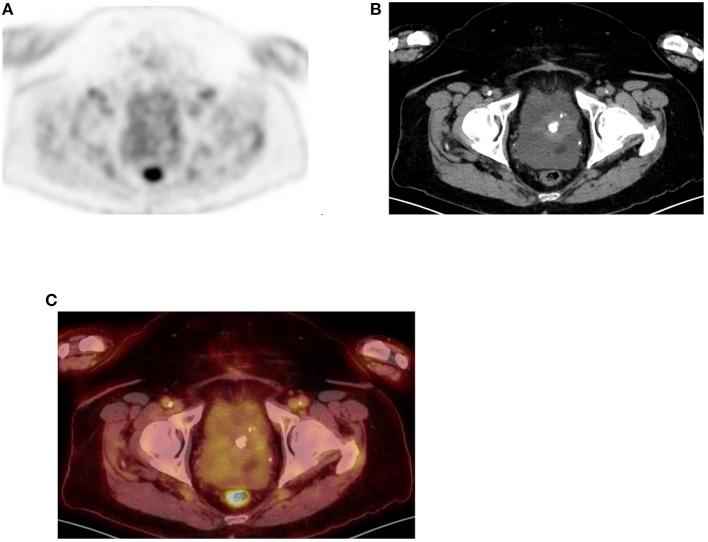

Since its introduction into clinical practice, multimodality imaging has revolutionized diagnostic imaging for both oncologic and non-oncologic pathologies. F-fluorodeoxyglucose (F-FDG) PET/CT imaging which takes advantage of increased anaerobic glycolysis that occurs in tumor cells (Warburg effect) has gained significant clinical relevance in the management of most, if not all oncologic conditions. Because FDG is taken by both normal and abnormal tissues, PET/CT imaging may demonstrate several normal variants and imaging pitfalls. These may ultimately impact disease detection and diagnostic accuracy. Imaging specialists (nuclear medicine physicians and radiologists) must demonstrate a thorough understanding of normal and physiologic variants in the distribution of F-FDG; including potential imaging pitfalls and technical artifacts to minimize misinterpretation of images. The normal physiologic course of F-FDG results in a variable degree of uptake in the stomach, liver, spleen, small and large bowel. Urinary excretion results in renal, ureteric, and urinary bladder uptake. Technical artifacts can occur due to motion, truncation as well as the effects of contrast agents and metallic hardware. Using pictorial illustrations, this paper aims to describe the variants of physiologic F-FDG uptake that may mimic pathology as well as potential benign conditions that may result in misinterpretation of PET/CT images in common oncologic conditions of the abdomen and pelvis.

自从多模态成像技术引入临床实践以来,它已经彻底改变了肿瘤和非肿瘤疾病的诊断成像。利用肿瘤细胞中发生的无氧糖酵解增加(瓦伯格效应)的F-氟脱氧葡萄糖(F-FDG)PET/CT成像,在大多数(即使不是全部)肿瘤疾病的管理中已具有重要的临床意义。由于正常组织和异常组织都会摄取FDG,PET/CT成像可能会显示出几种正常变异和成像陷阱。这些最终可能会影响疾病检测和诊断准确性。成像专家(核医学医师和放射科医生)必须充分了解F-FDG分布中的正常和生理变异;包括潜在的成像陷阱和技术伪影,以尽量减少对图像的错误解读。F-FDG的正常生理过程会导致胃、肝脏、脾脏、小肠和大肠出现不同程度的摄取。尿液排泄会导致肾脏、输尿管和膀胱摄取。由于运动、截断以及造影剂和金属硬件的影响,可能会出现技术伪影。本文旨在通过图片说明,描述可能模仿病变的生理性F-FDG摄取变异,以及在腹部和骨盆常见肿瘤疾病中可能导致PET/CT图像误判的潜在良性情况。